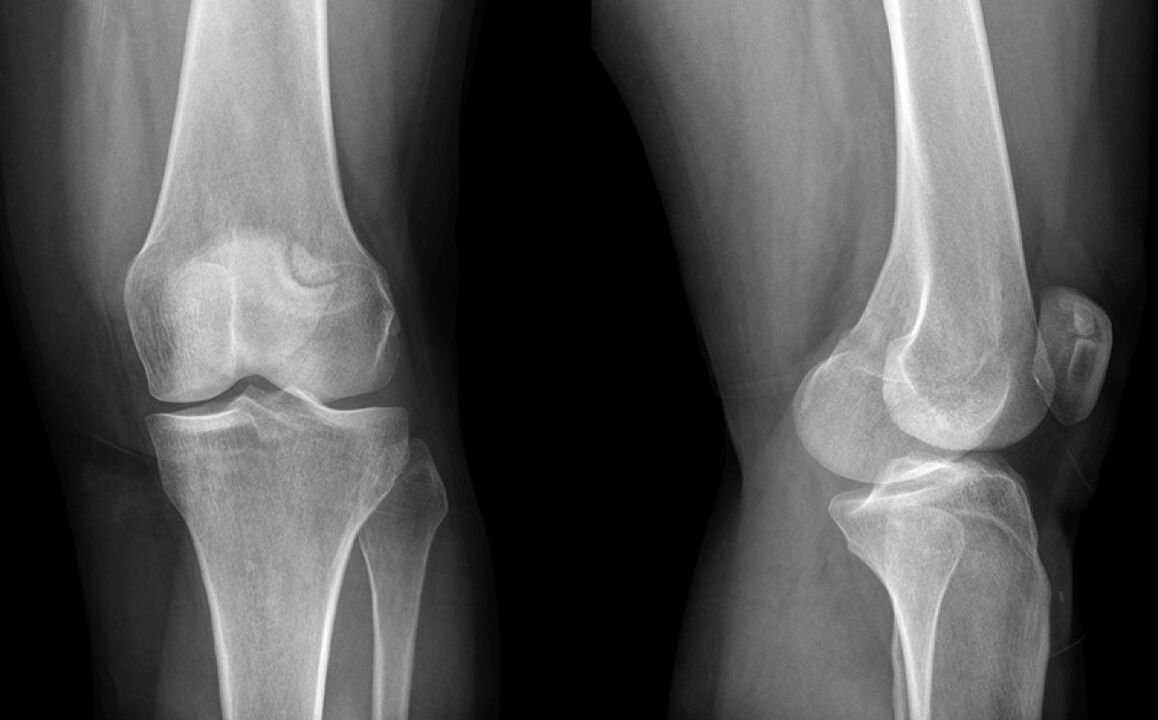

Il ginocchio ha ferito tre settimane. Alla fine, sono andato da un medico che sospettava il danno al menisco e veniva mandato a un raggio X. La diagnosi è lo stadio iniziale dell'artrosi dell'articolazione del ginocchio.